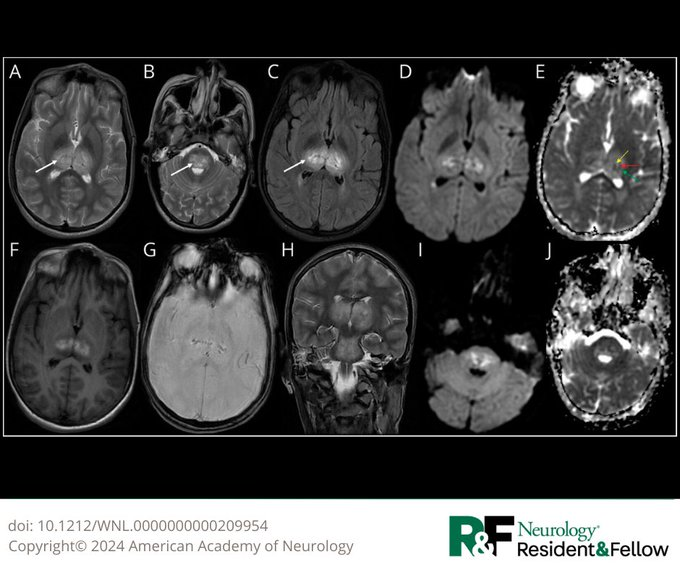

Neuro infection pearl RANBP2 mutations predispose patients to acute necrotizing encephalitis due to influenza A. Characteristic MRI involving thalami / brain stem/ cerebellum with lack of pleocyotsis is seen. Steroid responsive. https://t.co/kLEUy27g3Q. @AANmember @TheNewANA1

Tweet card summary image

pmc.ncbi.nlm.nih.gov

Acute necrotizing encephalopathy (ANEC) is a rare entity characterized by encephalopathy following a febrile illness. Most patients are sporadic; however, recurrent and familial cases have been...

Each month the Neurology Resident & Fellow Section editorial board selects their favorite article for the month. Read their current pick, "Child Neurology: Acute Necrotizing Encephalopathy of Childhood Associated With Dengue": https://t.co/PXkgNW6gG1 #NeurologyRF #NeuroTwitter

Child Neurology: Acute Necrotizing Encephalopathy of Childhood Associated With Dengue—Good Neurologic Outcome Despite a Fulminant Presentation https://t.co/o95oc0lclQ